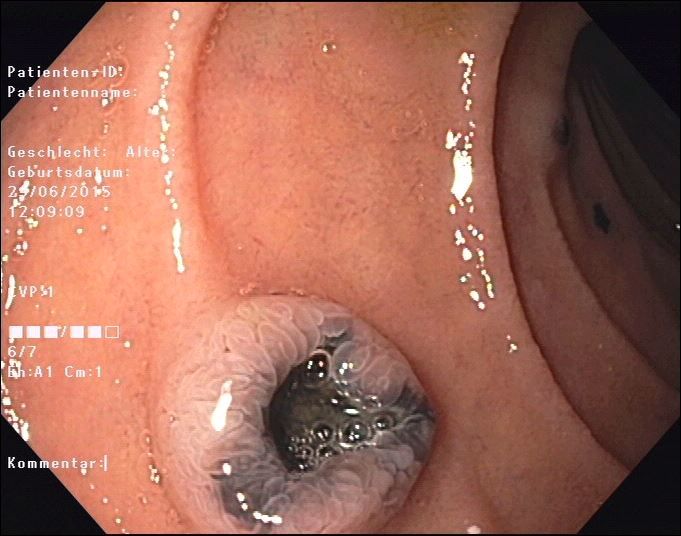

Unfortunately, the following endoscopy revealed multiple metastases in the stomach, duodenum and colon (Fig. 4-6) that endoscopically and histologically confirmed as metastasis of a malignant melanoma.

Figure 4: Polypoid melanoma metastasis in the duodenum. Note central depression as a sign of malignancy. The neighboring mucosa is completely preserved as well as the neighboring gallbladder wall in figure 1-3.